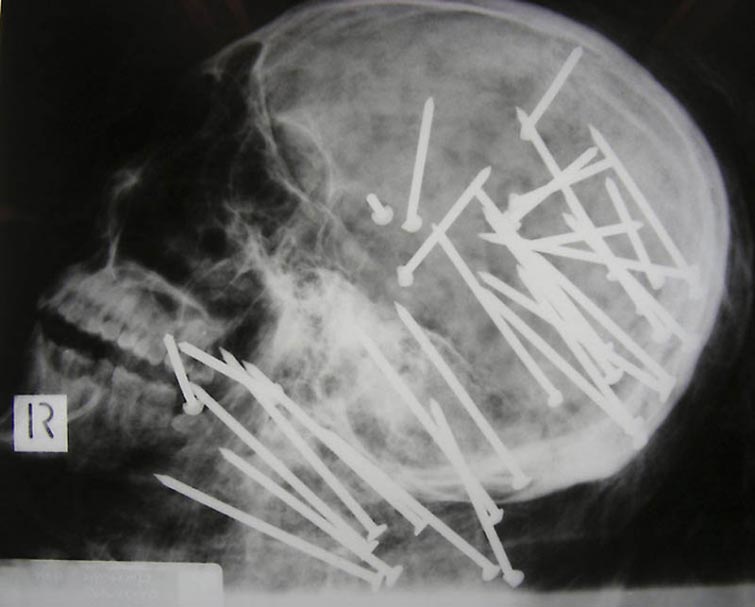

Череп китайского иммигранта Чен Лю, которому 34 раза выстрелили в голову из пневматического гвоздострела

Не трудно догадаться, что мужчина погиб